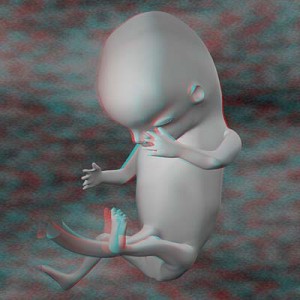

Дванадцятий тиждень вагітності

Відстань від тім'ячка до крижів приблизно 61 мм - для подання, це розмір великого курячого яйця. Вага плоду становить 9-13 м